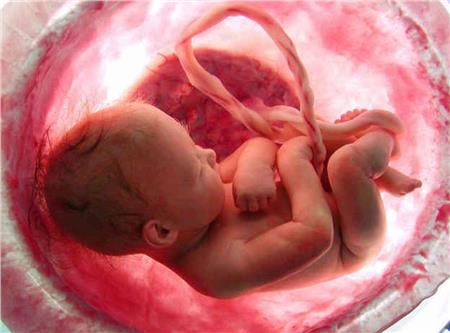

«Ἡ ἐπιστημονικὴ πρόοδος στὸν τομέα τῆς Ἐμβρυολογίας, ἀλλὰ καὶ ἡ τρισδιάστατη εἰκόνα τῶν ὑπερήχων πιστοποιοῦν τὴν ἀπὸ αἰῶνες διδασκαλία τῆς Ἐκκλησίας μας ὅτι ἡ ἀνθρώπινη ζωὴ ἀρχίζει «ἐξ ἄκρας συλλήψεως», δηλαδὴ τὴ στιγμὴ ποὺ τὰ 23 χρωμοσώματα τοῦ ὠαρίου ἑνώνονται μὲ τὰ 23 χρωμοσώματα τοῦ σπερματοζωαρίου καὶ δημιουργεῖται τὸ πρῶτο κύτταρο, τὸ ζυγωτό. Συγχρόνως, ὅμως, τότε σφραγίζεται καὶ ἡ προσωπικότητα τοῦ κάθε ἀνθρώπου, μὲ τὸ πλῆθος τῶν γονιδίων ποὺ παραλαμβάνει ἀπὸ τοὺς γονεῖς του.

Πρόσωπο μοναδικὸ καὶ ἀνεπανάληπτο θεωρεῖται τὸ ἔμβρυο καὶ ὡς τέτοιο ἀναγνωρίζεται παγκοσμίως. Ὡς «πρόσωπο» τὸ ἀναγνωρίζει καὶ τὸ Δίκαιο τῆς πατρίδας μας καὶ τὸ καθιστᾶ ὑποκείμενο καὶ φορέα ἀστικῶν δικαιωμάτων, π.χ. τὸ ἄρθρο 1711 τοῦ Ἀστικοῦ Κώδικα, σύμφωνα μὲ τὸ ὁποῖο τὸ συλληφθὲν ἔμβρυο μπορεῖ νὰ κληρονομήσει περιουσιακὰ στοιχεῖα συγγενῶν του, ἐὰν γεννηθεῖ ζωντανό.

Καὶ ἐνῶ καταβάλλονται τόσες προσπάθειες γιὰ τὴ δημιουργία καὶ ἀνθρώπινης ζωῆς (τεχνητὴ γονιμοποίηση, κλωνοποίηση), ἐντούτοις ἑκατομμύρια παιδιὰ θανατώνονται ἐν ψυχρῷ καὶ μάλιστα μὲ τὴν ψήφιση νόμων, ποὺ ἐπιτρέπουν τὴ θανάτωση τοῦ ἐμβρύου, μέχρι τὸν τρίτο μήνα τῆς κύησής του.